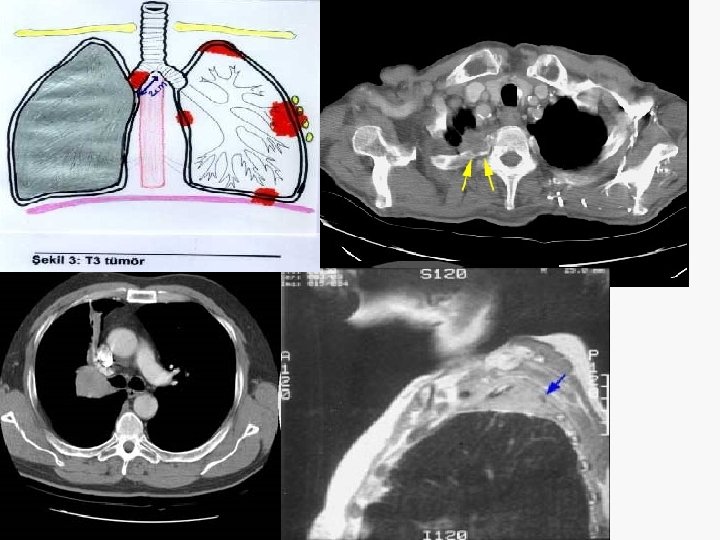

5. 4 cm

Evreleme EVRE 0 : Tis N 0 M 0 EVRE IA : T 1 N 0 M 0 EVRE IB : T 2 N 0 M 0 EVRE IIA : T 1 N 1 M 0 EVRE IIB : T 2 N 1 M 0 T 3 N 0 M 0 EVRE IIIA : T 1 -3 N 2 M 0 T 3 N 1 M 0 EVRE IIIB : T 4 N M 0 T N 3 M 0 EVRE IV : T N M 1

Göğüs duvarı invazyonu Evre IIB (T 3 N 0 M 0) Evre IIIA (T 3 N 1 M 0) Sadece parietal plevrayı tutan olgularda ekstraplevral rezeksiyon uygulanabilir. Daha derin invazyonlarda ‘en blok’’ rezeksiyon tercih edilmelidir. Tam rezeksiyon postop RT’ye gerek yok Cerrahi sınır (+) postop RT

Pancoast tümörü Potansiyel operabl olgularda mediastinoskopi T 3 N 0 -1 – Preop. KT + RT (40 -45 Gy) Cerrahi – Preop. RT (40 -45 Gy) Cerrahi T 4 ya da N 2 -3 – KT + RT (60 Gy)